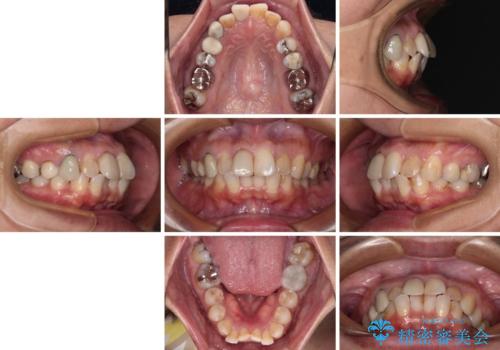

【モニター】処置歯の多い歯列 インビザラインでデコボコを整える

- 上下前歯のデコボコを気にして来院された患者様です。

歯列としては、ワイヤー装置でもインビザラインでも、どちらでも対応可能でしたが、処置されている歯が多く、ワイヤー装置を装着するためには処置歯のやり直しが必要な状態でした。

インビザラインでもアタッチメントを装着できないという同様のデメリットがありますが、比較的矯正治療を行いやすい歯列であったので、インビザラインによる矯正治療を行うこととしました。

術中や仕上がりに特に大きなトラブルはなく、スムーズに治療を終えることができました。